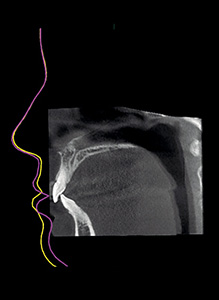

The 3D photo visualises soft tissue in relation to dentine and facial bones. As both a CBCT image and a 3D photo are generated in one imaging session, the patient position, facial expression, and muscle position remain unchanged – resulting in images that are perfectly compatible.

Measure distances and relationships between bone and soft tissue Measure distances and relationships between bone and soft tissue Measure distances and relationships between bone and soft tissue

Measure distances and relationships between bone and soft tissue

Superimpose images for comparisonSuperimpose images for comparison

Superimpose images for comparison